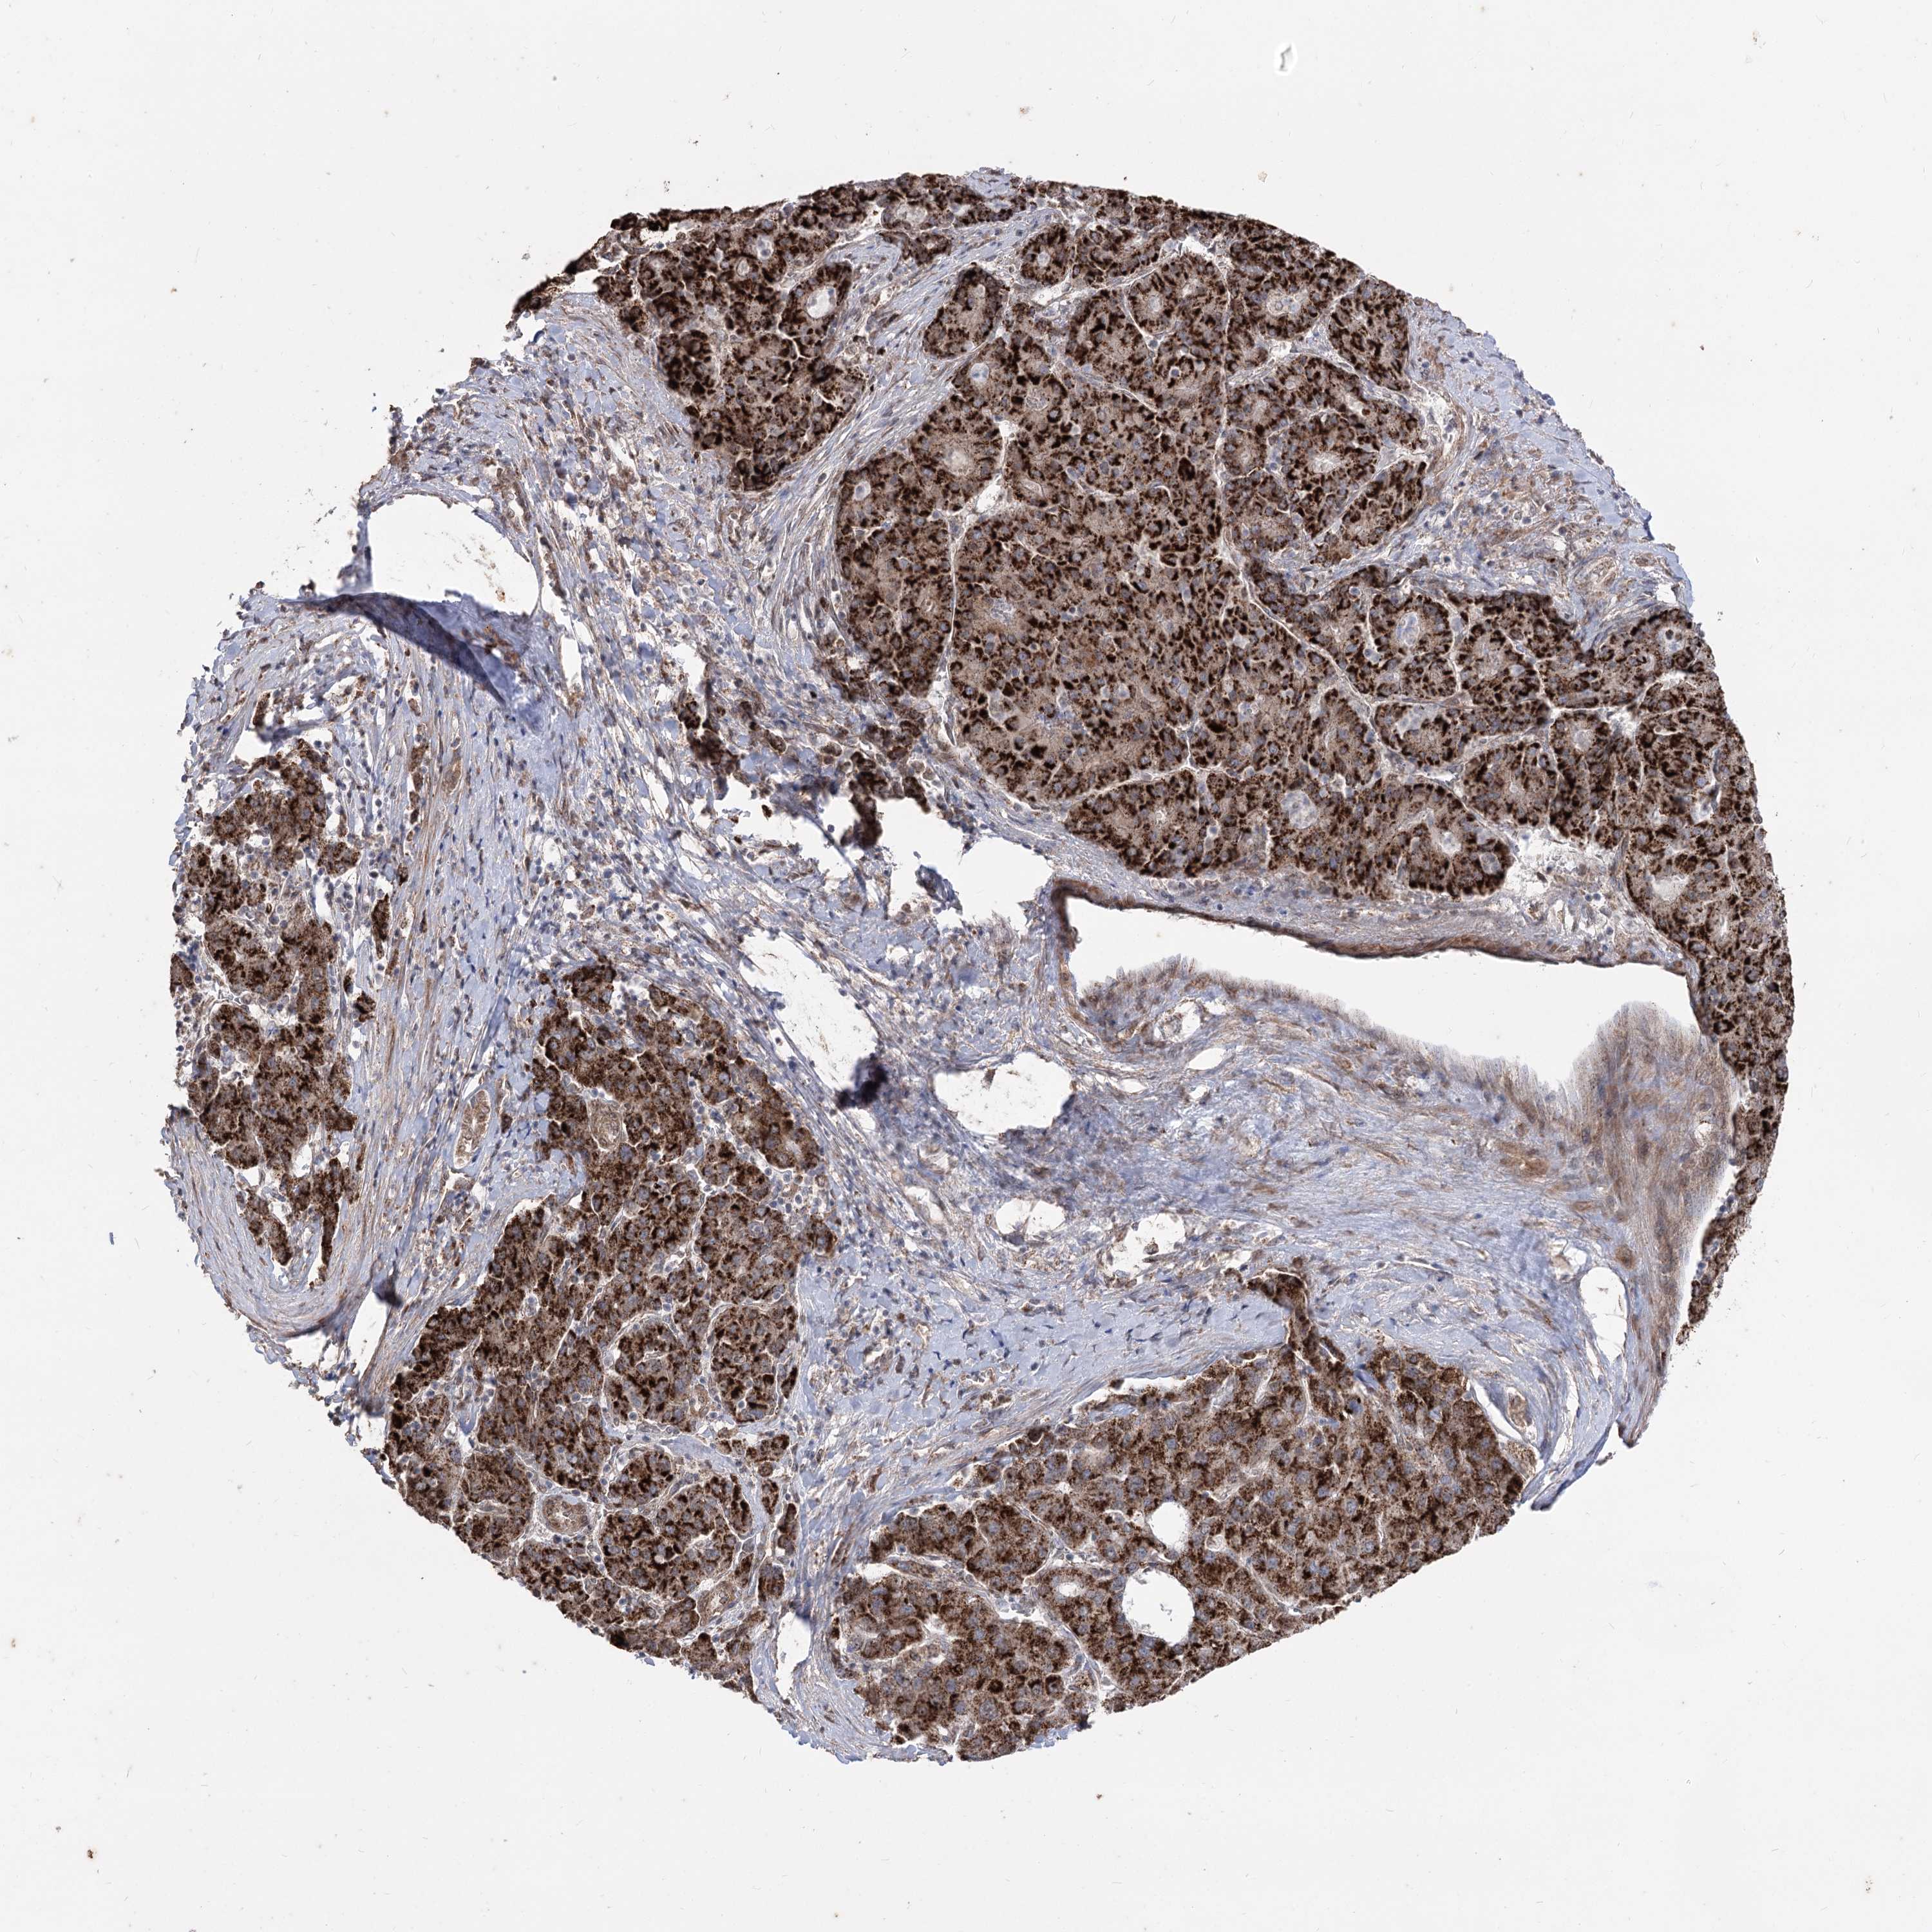

LIVER CANCER - Protein expressioni

A mouse-over function shows sample information and annotation data. Click on an image to view it in a full screen mode. Samples can be filtered based on level of antibody staining by selecting one or several of the following categories: high, medium, low and not detected. The assay and annotation is described here.

Note that samples used for immunohistochemistry by the Human Protein Atlas do not correspond to samples in the TCGA dataset.

Antibody stainingi

Antibody staining in the annotated cell types in the current human tissue is reported as not detected, low, medium, or high, based on conventional immunohistochemistry profiling in selected tissues. This score is based on the combination of the staining intensity and fraction of stained cells.

Each image is clickable and will lead to virtual microscopy that enables deeper exploration of all samples and also displays staining intensity scores, fraction scores and subcellular localization as well as patient and tissue information for each sample.

Antibody HPA035959

Antibody HPA035960

Staining

High

Medium

Low

Not detected

Intensity

Strong

Moderate

Weak

Negative

Quantity

>75%

75%-25%

<25%

None

Location

Nuclear

Cytoplasmic/membranous

Cytoplasmic/membranous,nuclear

Cholangiocarcinoma

Carcinoma, Hepatocellular, NOS